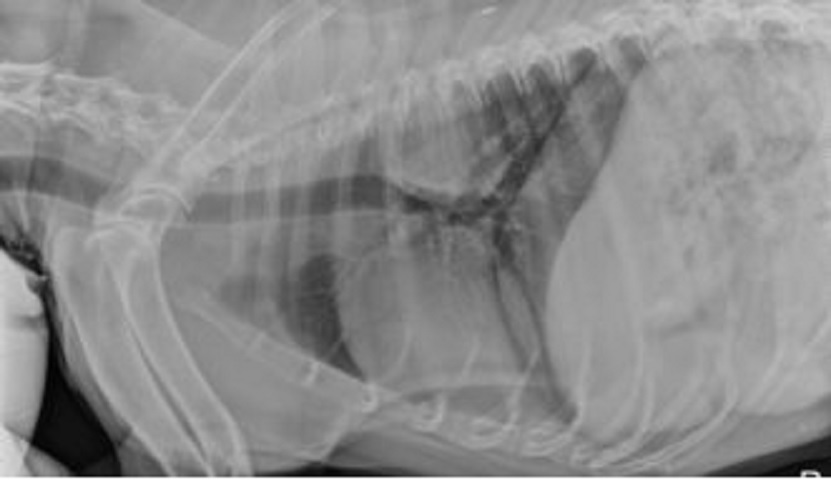

Veterinary radiography consists of diagnostic medical images generated in veterinary practice, including ultrasonography, CT, MRI, and nuclear imaging. It is essential in providing excess information by noninvasive means. Veterinary radiography is painless; however, sedation is often required to reduce anxiety and stress associated with the procedure in animals.